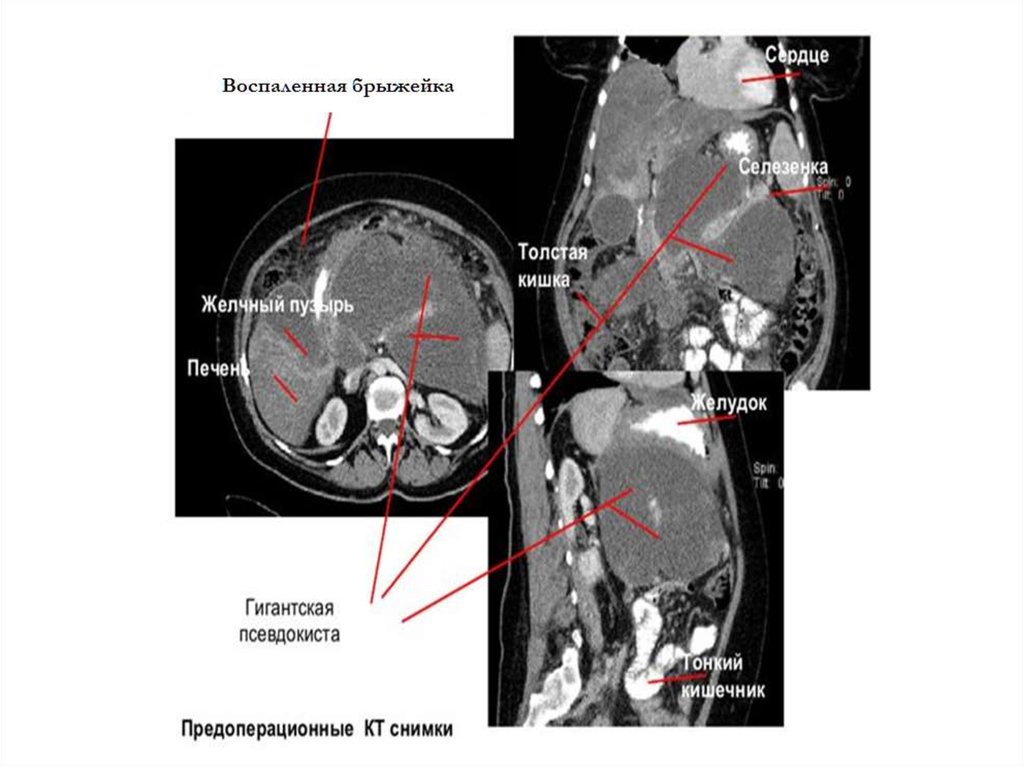

Дуоденумсохраняющие резекции головки ПЖ

должны выполняться при ХП с преимущественным поражением головки, верифицированном

клинико-инструментальными и морфологическими данными. Способ Бегера показан при малоизмененных протоках тела и хвоста. Бернский вариант менее сложен, но идентичен по отдалённым результатам. Способ Фрея выполняется при

расширенных протоках дистальных отделов или

при интрапанкреатических кистах головки. Дистальная резекция показана при изменениях дистальных отделов железы, кистах, свищах, аневризмах селезеночной артерии, при региональной

портальной гипертензии.